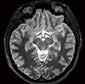

Gehirnblutung oder Gefäßverschluss

Handelt es sich um eine intrakranielle Blutung oder ist ein großes Gefäß verschlossen?

Ein Schlaganfall kann auf unterschiedliche Ursachen zurückzuführen sein. Deshalb ist es besonders wichtig, in kürzester Zeit über eine aussagekräftige Diagnostik zu verfügen.

Mit der Deep-Learning-basierten Auto-Stroke-Solution bringt Canon eine Lösung auf den Markt, die nicht nur selbstständig Bilder erstellt, sondern auch noch den Befundbericht dazu liefert.

Mit der Auto-Stroke-Solution präsentiert Canon eine Lösung, die in der Lage ist, ohne einen einzigen Klick unterschiedliche Arten von Schlaganfällen zu bestimmen und automatisiert eine detaillierte Auswertung zu erstellen. Um den Zustand des Schlaganfalls vollständig zu charakterisieren, analysiert das System, das auf Canons ebenfalls neuer Automation-Platform läuft, selbstständig CT-Scans. Den Notfallund Stroke-Teams werden in kürzester

Zeit Informationen zur Verfügung gestellt, die bei der klinischen Bewertung und Behandlung von Schlaganfällen helfen. „Die Auto-Stroke-Lösung integriert drei Schlaganfall-Applikationen, um sicherzustellen, dass die Untersuchung eine exakte Abbildung dessen liefert, was im Patienten vor sich geht“, beschreibt Michael Glasa, Produktmanager Healthcare IT und Manager Sales Support CT bei Canon Medical Systems, das neue System.

Diagnostik ohne Klick

Wenn die Zeit drängt, helfen die AutoStroke-Deep-Learning-Algorithmen bei Hirninfarktpatienten schnell, unterschiedliche Variationen einer intrakraniellen Blutung oder große Gefäßverschlüsse zu lokalisieren beziehungsweise die Penumbra und den potenziellen Infarktkern anzuzeigen. Denn die Kliniker benötigen schnellstmöglich Informationen, um in kurzer

jedes einzelne Pixel. Die Software stellt sogar selbstständig fest, ob die Untersuchung mit oder ohne Kontrastmittel durchgeführt wurde.“ Handelt es sich um eine Untersuchung ohne Kontrastmittel, sucht Auto-Stroke nach einer Gehirnblutung und erkennt selbstständig die unterschiedlichen Arten: subdural, epidural oder subarachnoidal. Wurde bei der Untersuchung Kontrastmittel verwendet, sucht die Maschine nach einem Gefäßverschluss. Und auch Perfusionsstudien werden automatisiert ausgewertet. Sowohl die ausgewerteten Bilder als auch die maschinell erstellten Reports werden direkt ins PACS geschickt. Man kann das System auch so einstellen, dass es den Report per E-Mail entweder an die behandelnden Ärzt*innen oder zusätzlich an die Radiolog*innen versendet. Im PDF-

Befundbericht sind in den Bildern die verdächtigen Areale markiert beziehungsweise farblich hervorgehoben, so dass leicht zu erkennen ist, wo eine Veränderung stattgefunden hat.

Hohe Sensitivität und Spezifität

Trotz der enormen Verlässlichkeit des Algorithmus liegt es an den weiterbehandelnden Ärzt*innen, das automatisiert erstellte Ergebnis zu validieren. Für die Analyse intrakranieller Blutungen wurde der Deep-LearningAlgorithmus anhand von mehr als 10.000 Fällen trainiert. Die gemessene Sensitivität beträgt 92 Prozent und die Spezifität erreicht einen Wert von 97,5 Prozent. Bei der Unterscheidung von Gefäßverschlüssen liegen die Werte von Sensitivität und Spezifität

bei jeweils 98 Prozent. Bei der CT-Perfusionsmessung nutzt die Anwendung die Bayesischen CTP+-Algorithmen, um die Penumbra und den Infarktkern ohne einen einzigen Klick zu quantifizieren. Dabei können nicht nur 2D-, sondern auch 4D-Studien gleichermaßen ausgewertet werden. Der große Vorteil von Auto-Stroke besteht darin, dass die Kliniker*innen innerhalb kürzester Zeit einen kompletten Befundbericht zugeschickt bekommen, um schnell die richtige Therapie-Entscheidung treffen zu können. Das System ist in der Lage, innerhalb eines Zeitraums von etwa 30 bis maximal 60 Sekunden automatisiert und mit hoher Zuverlässigkeit Schädel-CT-Scans auszuwerten und unterschiedliche Arten von Schlaganfällen zu differenzieren. //